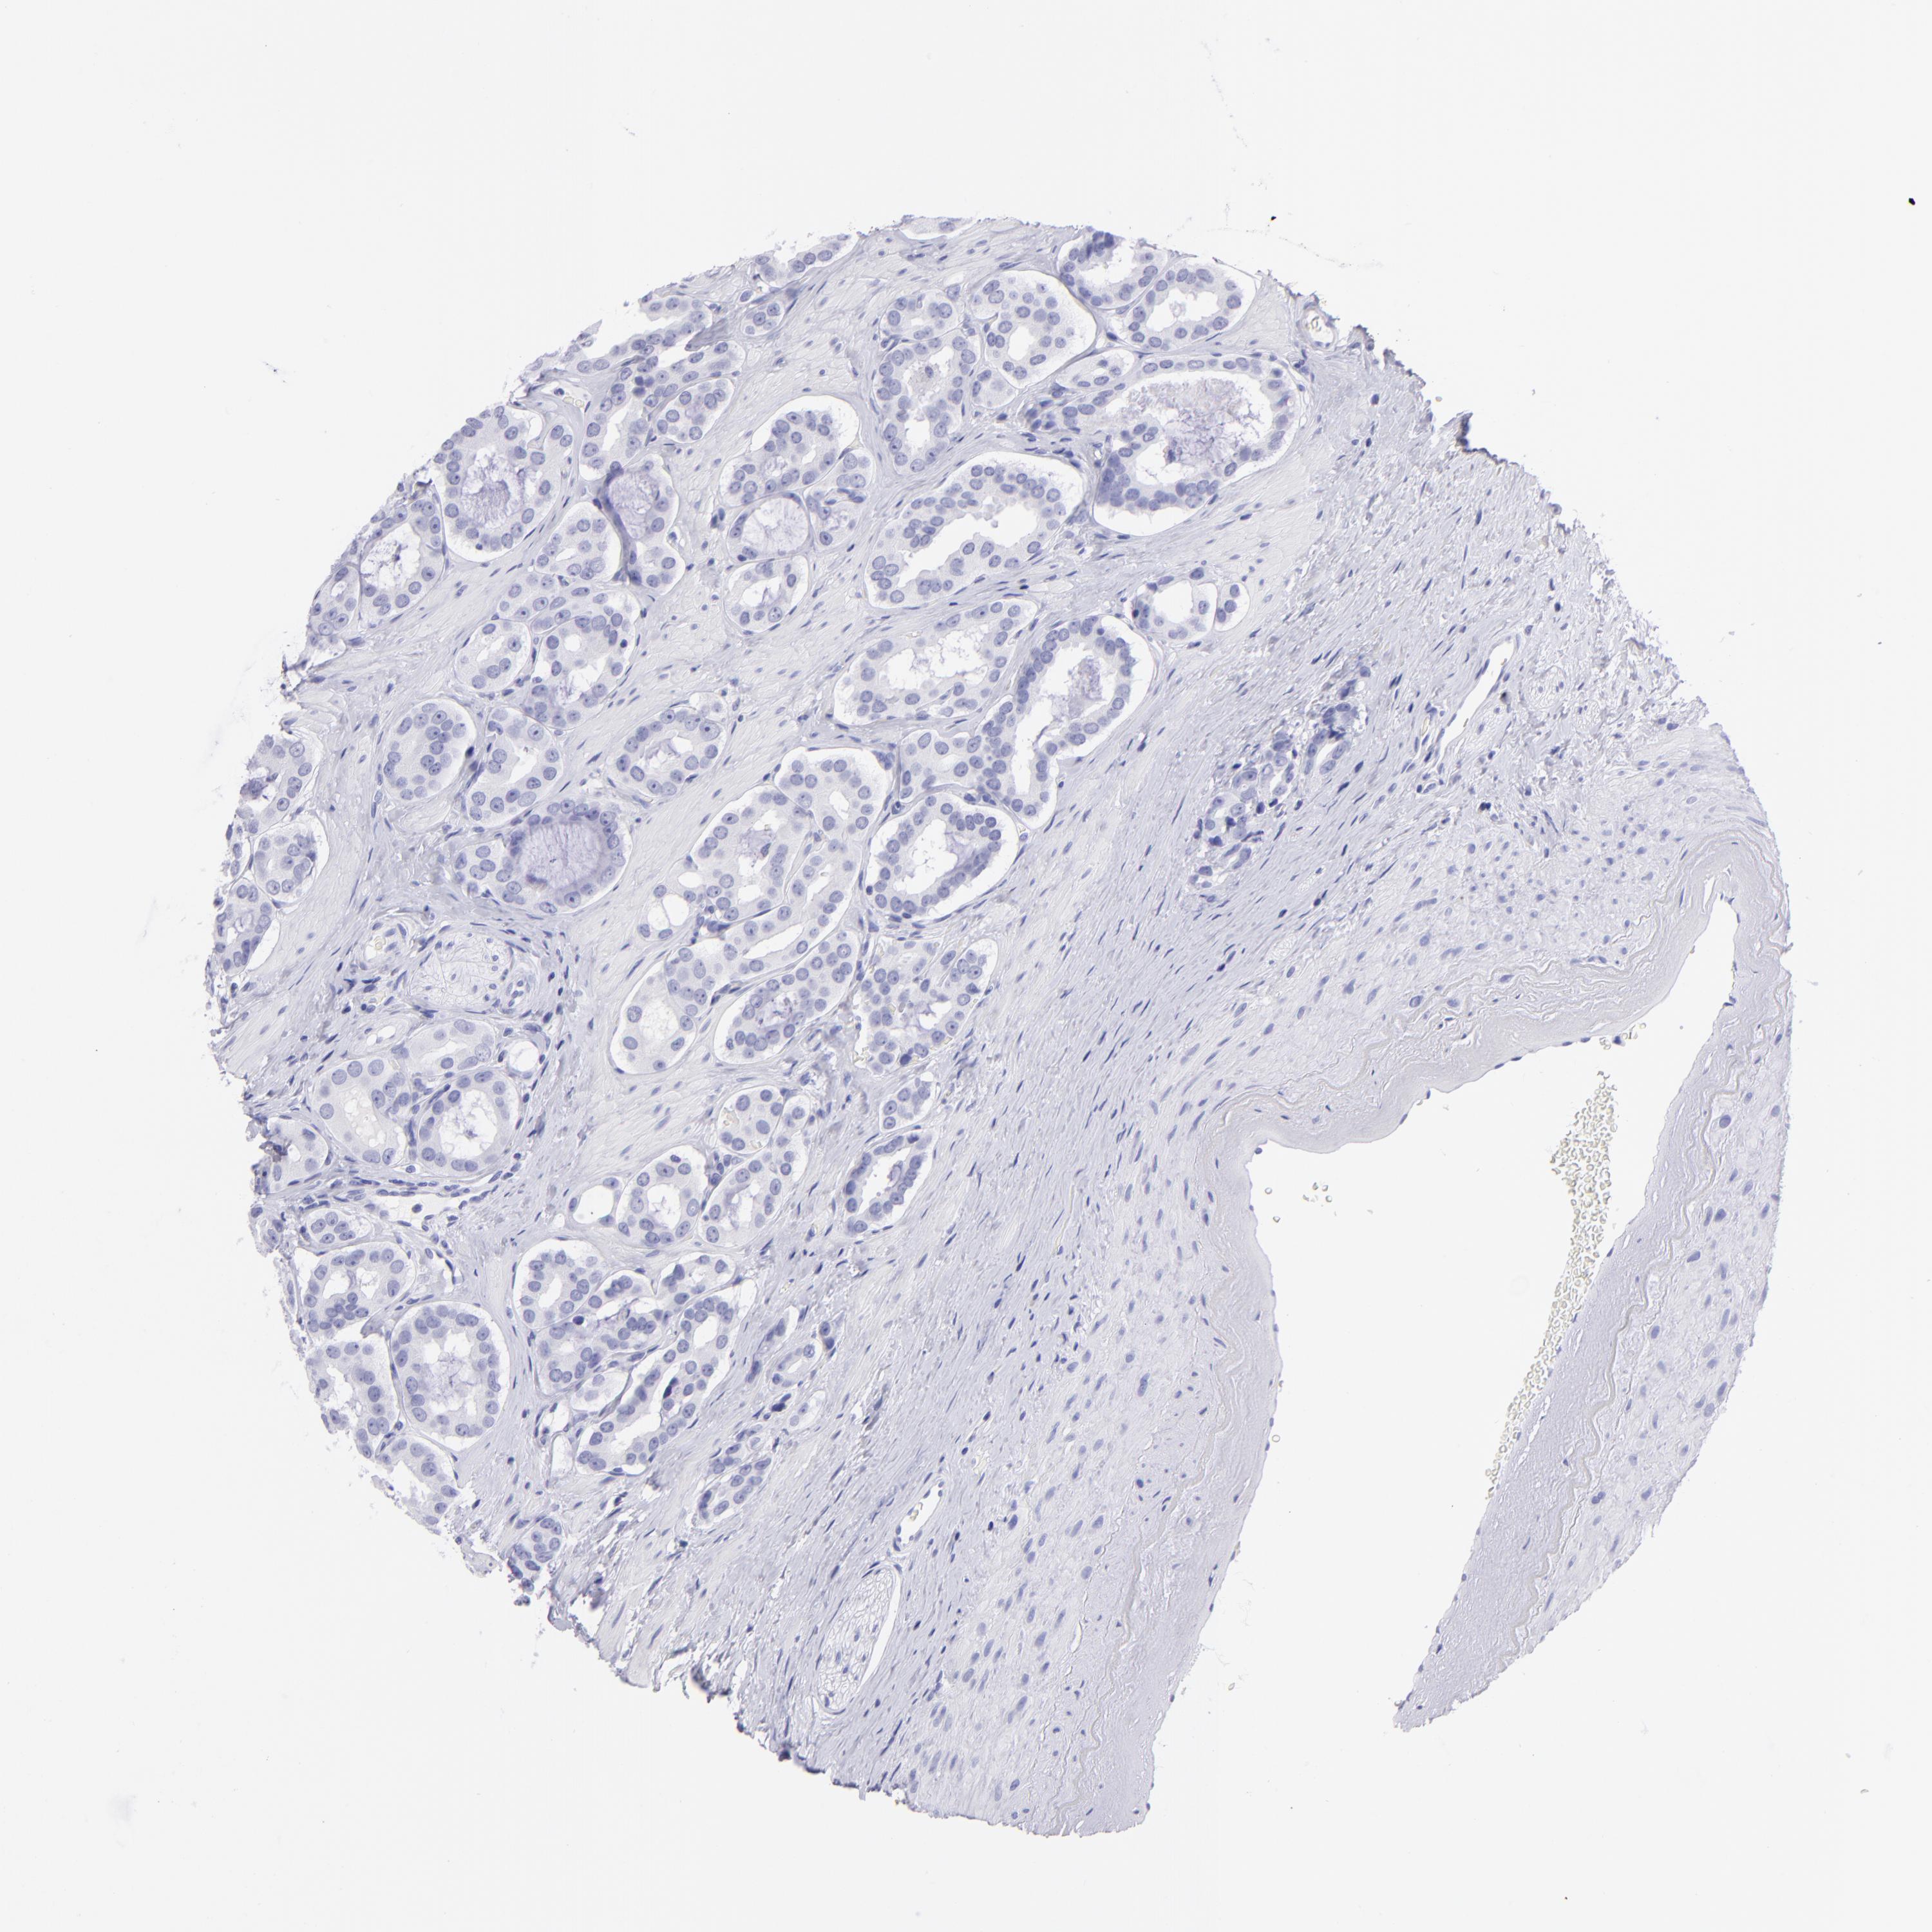

PROSTATE CANCER - Protein expressioni

A mouse-over function shows sample information and annotation data. Click on an image to view it in a full screen mode. Samples can be filtered based on level of antibody staining by selecting one or several of the following categories: high, medium, low and not detected. The assay and annotation is described here.

Antibody stainingi

Antibody staining in the annotated cell types in the current human tissue is reported as not detected, low, medium, or high, based on conventional immunohistochemistry profiling in selected tissues. This score is based on the combination of the staining intensity and fraction of stained cells.

Each image is clickable and will lead to virtual microscopy that enables deeper exploration of all samples and also displays staining intensity scores, fraction scores and subcellular localization as well as patient and tissue information for each sample.

Antibody HPA009177

Antibody CAB002661

Adenocarcinoma, Low grade

Adenocarcinoma, High grade

Adenocarcinoma, Medium grade